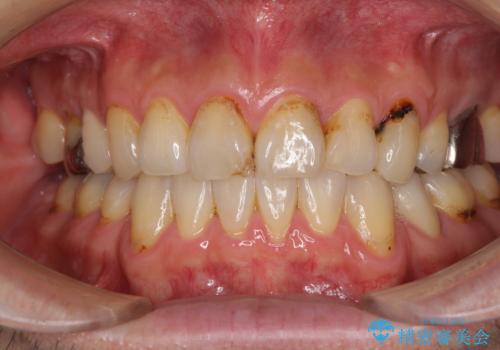

- むし歯による奥歯の痛みを気にして来院された患者様です。

神経にまでむし歯の及んでいる歯や、既に根管治療がされている歯に痛みがあったため、まずは根管治療を行うこととしました。

その後、以前行った抜歯矯正の後戻りをインビザライン・ライトにより改善し、むし歯や銀歯はオールセラミッククラウンにて補綴治療することとしました。

痛みは速やかに引き、銀歯や黒く変色したむし歯がセラミッククラウンで自然な色合いに仕上がり、患者様には大変満足していただきました。